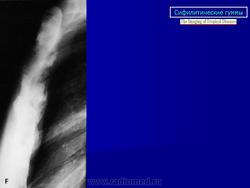

Гуммозный периостит наблюдается в излюбленном месте, в диафизе (чаще большеберцовой кости) - в оссифицированном периосте определяется одна или несколько гумм овальной или округлой формы. На рентгенограммах обычно на уровне диафиза отмечается ограниченное утолщение кости в форме полуверетена за счет утолщения периоста с гладким наружным контуром. Гумма - одна или несколько в виде очага деструкции (размерами не более 1,5-2 см) располагается в самом центральном месте остеофита, непосредственно под надкостницей, с четкими склерозированными контурами.

Диффузный сифилитический остеопериостит при позднем врожденном сифилисе по частоте поражения занимает 1 место. Поражается преимущественно большеберцовая кость. На рентгенограммах утолщенная окостеневшая надкостница сливается с корковым слоем. Во всех слоях кости - массивный склероз, кость на большом протяжении теряет свою структуру. Наружный контур четкий, но может быть несколько волнистым. Среди склероза могут наблюдаться очажки деструкции за счет миллиарных гумм - это сочетание множественного гуммозного и диффузного сифилитического периостита.

При локализации процесса в большеберцовой кости отмечается характерная картина «саблевидной голени» (кость удлинена, утолщена, изгибается кпереди). Редко встречаются «гребневидные» периоститы с наличием поперечных полос, напоминающих зубцы гребня, и «кружевные» периоститы - сочетание слоистого и гребневого периостита, что напоминает кружево. Наружние контуры, как правило, зазубрены.

Раньше работала в больнице, где было отделение по выхаживанию новорожденных. Очень часто встречалась с врожденным сифилисом, которого с каждым годом становится все больше и больше. Основными проявлениями были остеохондрит и сифилитический периостит. Вот несколько снимочков с этой патологией, быть может, кто-то не встречался с ней.